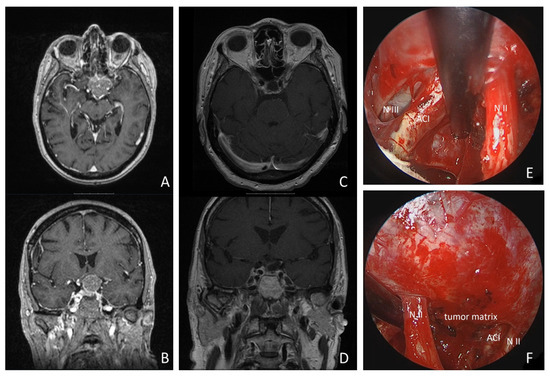

A 68-year-old woman presented with progressive left-sided visual dysfunction. The MR imaging showed a 26 × 30 × 24 mm lesion on the tuberculum sellae with compression of the optic chiasm and extending around the left internal carotid artery. Gross total resection was achieved via a supraorbital keyhole craniotomy. Histopathology confirmed a WHO Grade I meningotheliomatous meningioma. The patient’s visual loss improved within the first postoperative week, and pituitary function remained stable. The follow-up MR imaging at 3 and 24 months postoperatively showed no residual tumor tissue or recurrence (details are shown in Figure 5 and Supplementary Video S1).

Figure 5.

Illustrative case: a 68-year-old woman presented with progressive left-sided visual loss over 1 month. MRI revealed a 26 × 30 × 24 mm tumorous lesion on the tuberculum sellae, compressing the optic chiasm and extending around the left internal carotid artery (see MR imaging axial: (A), coronal: (B)). Postoperative MRI revealed no residual tumor tissue (see (C,D)). Gross total resection was achieved using a supraorbital keyhole approach with endoscopic assistance. Intraoperative inspection of the opticocarotid window with a 30° endoscope is shown (see (E)). (N II: left optic nerve; ACI: internal carotid artery; N III: N. oculomotorius). * = remnant tumor tissue. (F): intraoperative inspection of intrasellar region with 30° endoscope (N II: left optic nerve; ACI: internal carotid artery).